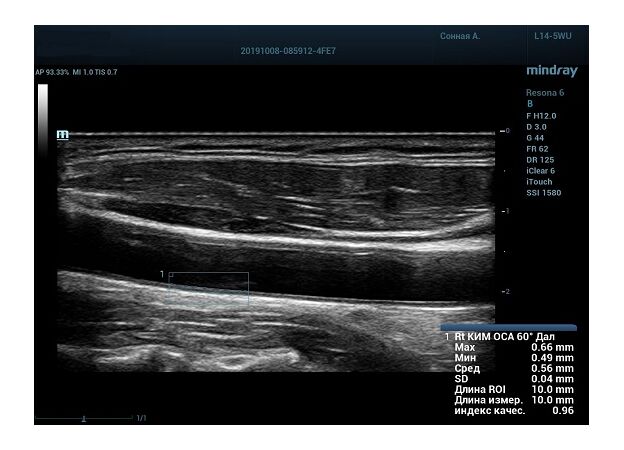

Также данный параметр используется для диагностики гипертензивной и атеросклеротической ангиопатии. Методика включает в себя измерение IMT проксимального, среднего и дистального отдела общей сонной артерии, каротидной луковицы, проксимального и среднего отдела внутренней сонной артерии. Далее вычисляем среднее значение и сравниванием с критериями Intima-mediathickness: Appropriate evaluation and proper measurement (ESC 2015, EAUD 2019) по центильной системе с привязкой к полу и возрасту.

На сегодняшний день измерение IMT происходит автоматическим путем при использовании функции AUTO-IMT. Необходимо указать прибору зону интереса, стандартной длиной (1 см), в которой происходит отслеживание кромок и выдача максимального, среднего и минимального значения.

УЗИ аппараты компании Mindray среднего, экспертного и премиального класса снабжены данной функцией и позволяют контролировать не только полученные значения, но и оценить точность измерения кромки в конкретной зоне по индексу качества. Используя индекс качества, легко решить, можно ли использовать полученное значение.